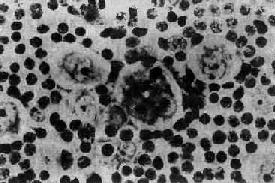

何杰金病的肿瘤成分中除典型的R-S细胞外,还有一些肿瘤细胞,形态与R-S细胞相似,但只有一个核,内有大形核仁,称为何杰金细胞。这种细胞可能是R-S细胞的变异型,不能作为诊断的依据。此外,还有一些变异的R-S细胞常见于本病的某些特殊类型:①有些细胞体积较大,胞浆淡染,核大,常扭曲,呈折叠状或分叶状;核膜薄,染色质细,核仁小,可有多个小核仁。这种细胞常见于淋巴细胞为主型何杰金病。②陷窝细胞(lacunar cell)多见于结节硬化型何杰金病。细胞体积大,胞浆丰富,染色淡或清亮透明,核大呈分叶状,常有多个小核仁。用福尔马林固定的组织,细胞浆收缩与周围细胞之间形成透明的空隙,好似细胞位于陷窝内故称陷窝细胞(图11-2)。③多形性或未分化型细胞,多见于淋巴细胞消减型何杰金病。细胞体积大,大小形态多不规则;核大,形状不规则,核膜厚,染色质粗,常有明显的大形核仁,核分裂像多见,并常有多极核分裂。

图11-2 何杰金病示陷窝细胞